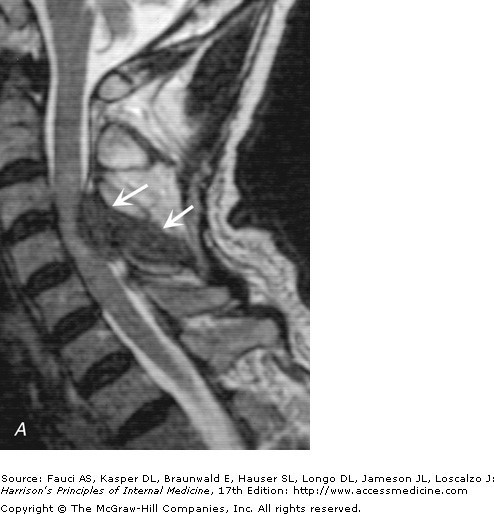

Intramedullary Tuberculoma in a 45year-old apparently healthy Nigerian